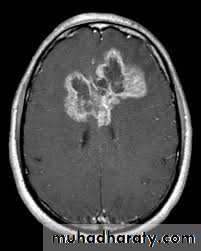

Glioma

Comments primary interracial tumor , vary greatly in malignancy , have many names depending on the histological type :

astrocytoma

oligodendroglioma both of them are well differentiated slowly growing t.

gliobtastoma multiforme G IV highly malignant t. named also as butterfly G. arise from the anterior or posterior aspect of the corpus callosum , extend & spread to both cerebral hemispheric sides

grading of malignancy of G. depending on the following :

well defined or irregularity of the lesion

surrounding edema present or absent

associated shifting of midline & crossed midline lesion

contrast enhancement

associated hemorrhage , necrosis , & cystic formation

seeding via csf & dissemination .

Low grade G. I well or ill defined lesion iso dence to the brain tissues , not associated with oedeme , no Enhancement , no associated Hemorrhage , necrosis .

From G II , III, various previous finding

IV( glioblastoma multiforme ) are highly malignant have all previous mentioned features .